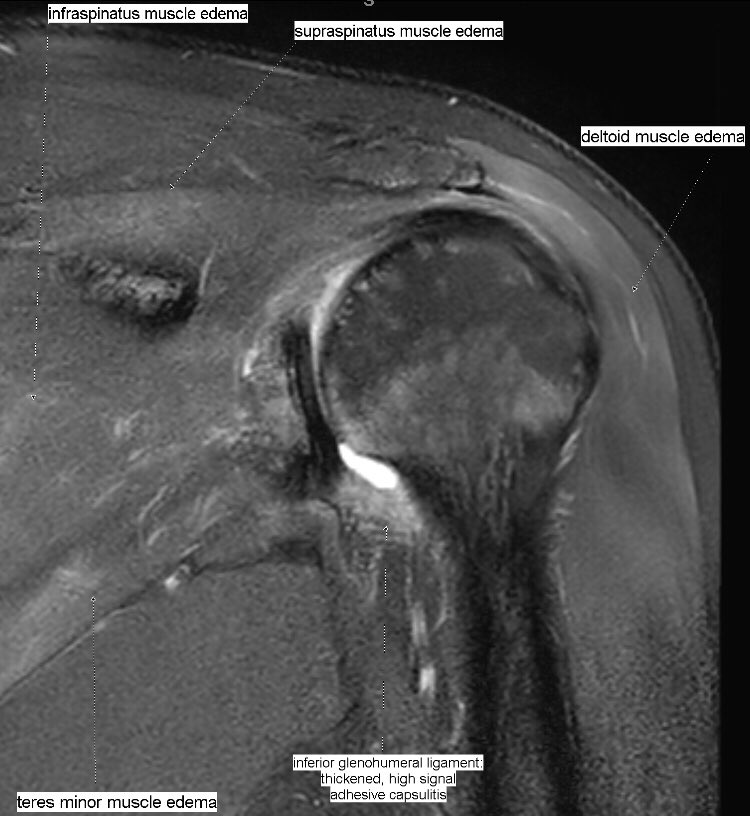

Edema + patchy fatty infiltration of supraspinatus, infraspinatus, deltoid and teres minor muscles. Parsonage-Turner syndrome (acute brachial plexus neuritis) of suprascapular + axillary nerves. Associated adhesive capsulitis.

#MSKrad#shoulder#orthotwitterpic.twitter.com/1C0f9g30Ad